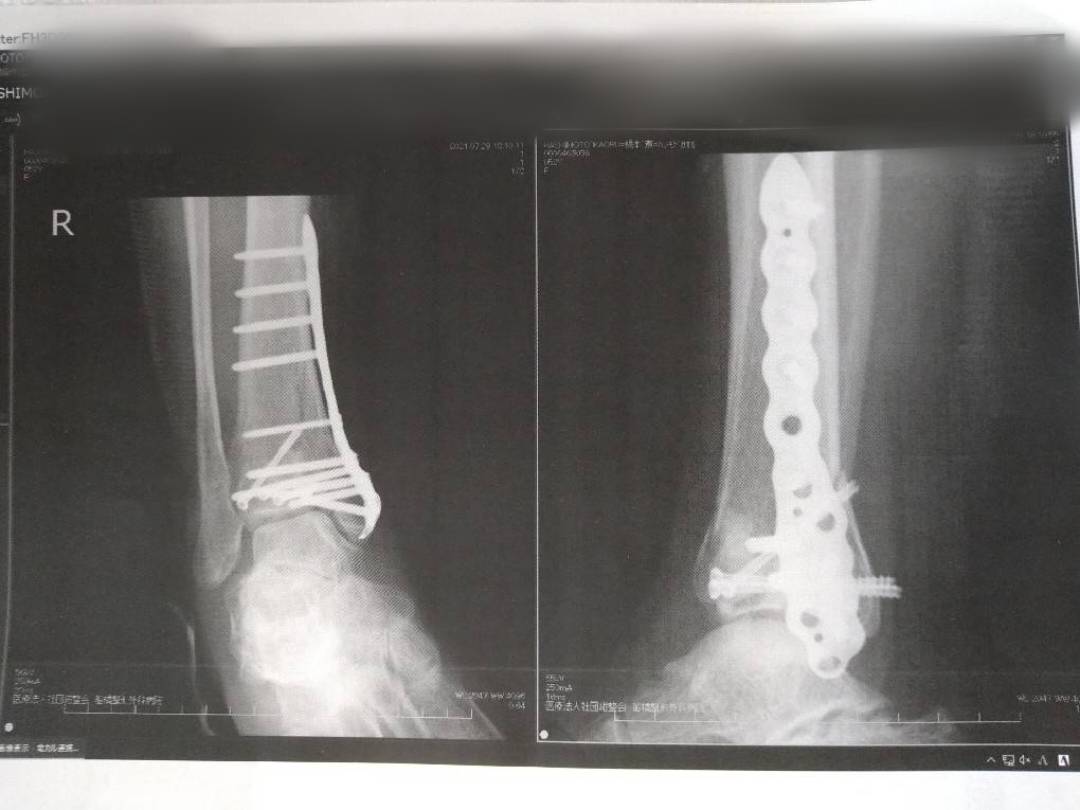

KAORU そうですね。ここまできたら、(試合が)できるようになるまで休んでいいかなって。私のように体のなかにプレートやスクリューなどの異物が入っていると、痛みはずっと残るんですね。大腿骨も、踵もそう。それがなくなると、痛みが嘘みたいに消える。先生に「これを抜いたあとで引退するとなれば、どれぐらいになりますか?」って聞いたら、「8月8日は無理だね」と言われたので、8月8日は入れたまま試合をやります。